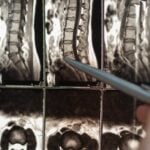

Ce este spondiloza cervicală?

Spondiloza cervicală este o condiție degenerativă a coloanei vertebrale cervicale, caracterizată prin modificări ale articulațiilor și discurilor intervertebrale. Aceste schimbări apar de obicei odată cu înaintarea în vârstă și pot duce la compresia nervilor și a măduvei spinării. Această afecțiune poate fi rezultatul uzurii normale a coloanei vertebrale sau a leziunilor vechi. Ești predispus la această condiție dacă ai un istoric de muncă solicitantă fizic, leziuni cervicale anterioare sau ești supraponderal.